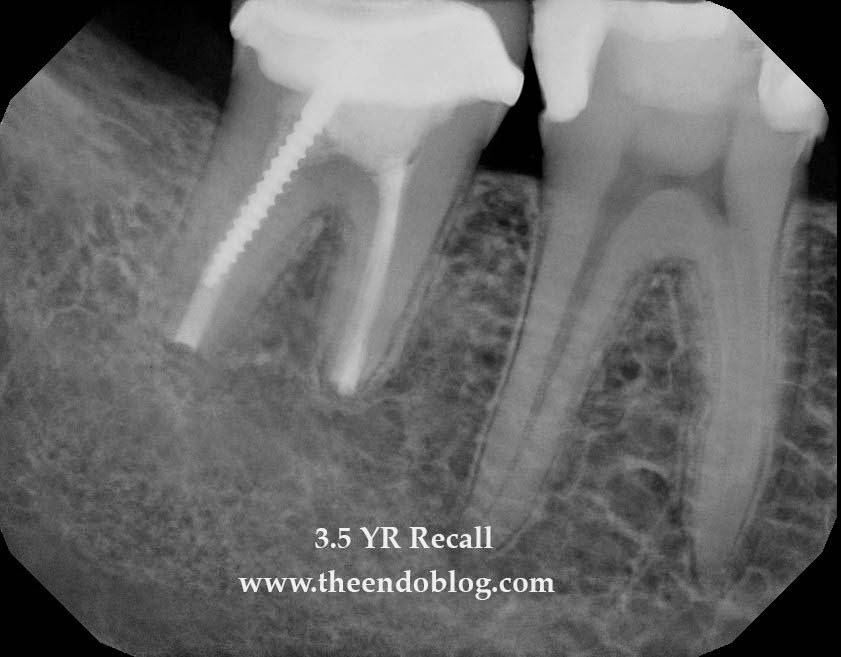

Note the bone levels around the tooth. They are identical to the pre-op bone levels. Intentional replantation has preserved the natural tooth AND the periodontium.

Previous posts have discussed the often overlooked surgical option of intentional replantation. The following case is an example of 3.5 yr success of intentional replantation of a Md second molar.